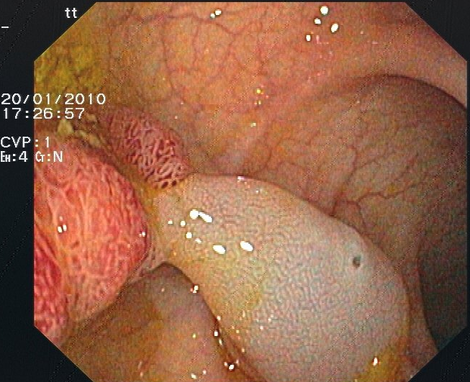

Chromoendoskopie

Manche Schleimhautveränderungen im Magen-Darm-Trakt sind bei der Endoskopie nur schwer zu erkennen bzw. abzugrenzen. Bei der Chromoendoskopie werden Farbstoffe auf die Schleimhaut aufgesprüht, dadurch werden Schleimhautveränderungen besser hervorgehoben. Proben können dann gezielt entnommen werden.

Eingesetzt werden absorptive Färbemittel, die von bestimmten Zellen aufgenommen werden, und Kontrastfärbemittel, die sich auf die Schleimhaut auflagern und das Schleimhautrelief verdeutlichen.

Als Kontrastfärbemittel wird im oberen und unteren Gastrointestinaltrakt zur besseren Erkennung und Abgrenzung von Polypen bzw. Krebsvorstufen Indigokarmin verwendet (Abbildung 1). Essigsäure wird in der Speiseröhre zur besseren Beurteilbarkeit eines Barrett-Ösophagus aufgebracht (diese Veränderung gilt ebenfalls als Krebsvorstufe).